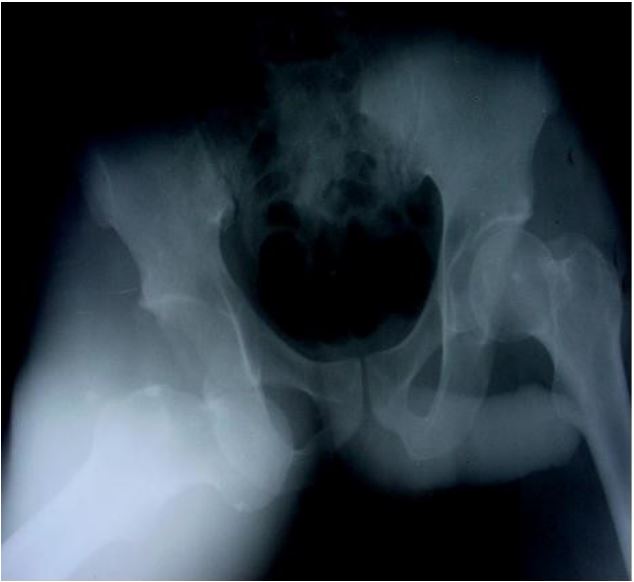

Case 1: Mr. BA was a 29-year-old patient who was hospitalized in October 2000 following a road traffic accident. He was sitting behind the driver when his right knee hit the driver’s seat. On admission, the same limb was abducted, externally rotated and flexed at the hip. An anteroposterior radiograph of the pelvis revealed a right obturator dislocation (Figure 1) associated with a left supracondylar open fracture. Treatment consisted of closed reduction. The hip was stable afterward. The left supracondylar open fracture was treated surgically. Weight bearing on the dislocated limb was authorized after 6 weeks of bed traction. Thirty nine months later, the right hip is mobile, painless and normal on plain X-rays.

Figure 1: Anteroposterior X-ray of the pelvis showing a right obturator dislocation (patient 1).